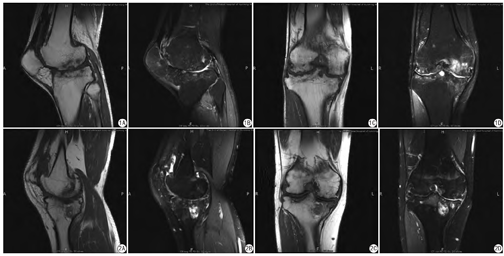

病例1,患者,男性,43岁,“因反复黑便2年,伴呕血3次”入院,两年前无明显诱因出现黑便,当地医院胃镜提示十二指肠球后溃疡并出血,反复治疗无效后至我院就诊,行走入院,否认遗传倾向性疾病及传染病家族史。查体:贫血貌,巩膜无黄染,全身皮肤黏膜无瘀点瘀斑,全身浅表淋巴结无肿大,胸骨无压痛,双肺呼吸音清晰,未闻及干湿啰音,心律齐,未闻及杂音,腹平软,无压痛,肝脾无肿大,双下肢无水肿,右上肢肘关节活动受限,双下肢关节畸形,伴活动受限;肌力、肌张力正常。实验室检查:白细胞4.1×109/L[参考范围:(3.5~ 9.5)×109/L],红细胞2.79×1012/L[参考范围:(3.8~ 5.1)×1012/L],血红蛋白84 g/L[参考范围:(115~ 150) g/L],血小板244×109/L[参考范围:(125~350)×109/L],网织红细胞比值为7.13%(参考范围:5%~15%),网织红细胞绝对值198.9×109/L[参考范围:(24~ 84)×109/L],尿酮体阳性,粪便常规及隐血实验:颜色棕黑,性状稀,隐血实验(+),活化部分凝血活酶时间(activated partial thromboplastin time,APTT) 103.5 s(参考范围:男性31.5~43.5 s;女性32~43 s),FIB 8.18 g/L(参考范围:1.75~5.54/L),VⅢ因子活性600% (参考范围:77.3%~128.7%),IX因子活性1%(参考范围:67.7%~128.5%)。MRI所见:T1加权像(T1WI)矢状位、冠状位(图1A、图1C)示:左膝关节间隙狭窄,髌骨形态增大并向前突出,关节构成诸骨边缘骨质增生变尖,关节面下骨质侵蚀、破坏、缺损,髁间窝加深;质子密度加权像(proton density weighted image,PDWI)矢状位、冠状位(图1B、图1D)示:左侧股骨下段、左侧胫骨上段见多发斑片、片状稍长T2信号及多发大小不等类圆形长T2信号。左膝关节滑膜增厚,骨软骨变薄、缺损;内外侧半月板显示不清;前、后交叉韧带肿胀见斑片状稍长T2信号。结合临床及实验室检查,诊断为血友病性关节炎。

病例2,患者,男性,25岁。因“反复鼻,皮肤瘀斑20余年,右膝关节肿痛1 d”入院,因“右膝关节滑膜炎”至外院就诊,诊断为血友病,否认遗传倾向性疾病及传染病家族史。查体:患者体温、呼吸、脉搏均无明显异常,右膝关节肿胀、压痛明显(评估疼痛评分5分,严重程度为中度)。白细胞4.78×109/L[参考范围:(3.5~ 9.5)×109/L],血红蛋白170 g/L(参考范围:115~ 150 g/L),血小板178×109/L[参考范围:(125~ 350)×109/L],凝血因子IX活性25.8%(参考范围:67.7%~128.5%)。MRI所见:T1WI矢状位、冠状位(图2A、图2C)示:右膝关节毗邻正常,关节间隙变窄,关节构成诸骨边缘骨质增生变尖,关节面下骨质侵蚀、破坏、缺损。PDWI矢状位、冠状位(图2B、图2D)示:股骨下段、胫骨上段骨质见片状稍长T2信号,胫骨平台骨质见多发类圆形长T2信号,股骨下端及胫骨平台软骨缺损。外侧半月板前角及内侧半月板后角内见线状稍长T2信号,未达关节面,髌上囊及关节腔内少量积液。综上,实验室指标诊断为轻型血友病B型,影像学诊断为符合血友病性关节炎影像表现。该病例较特殊,因患者凝血因子活性较高,为临床轻度血友病,但影像学所示关节炎严重程度较重,与血友病病程严重程度不符。本病例提示血友病性关节炎所致的关节损伤程度可与血友病病程的严重程度不一致,严重关节破坏可在轻型血友病患者中出现。